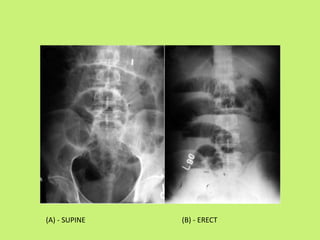

Plain X-ray of abdomen & chest :

• Plain X-ray abdomen may show presence of multiple

air fluid levels and dilated loops of gut in case of acute

or sub-acute obstruction.

• Calcification in the abdominal lymph nodes also

indicates TB.

• Plain X-ray chest done simultaneously but remind this,

normal CXR doesn’t rule out the diagnosis.

(A) - SUPINE (B) - ERECT